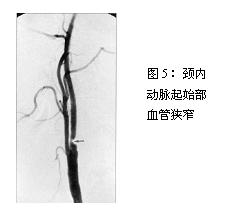

若怀疑颅内外动脉疾病,可进行非侵入性动脉影像检查,如颈部动脉超声、经颅多普勒超声(TCD)、磁共振成像血管造影(MRA),必要时行数字减影血管造影(DSA,图5)。